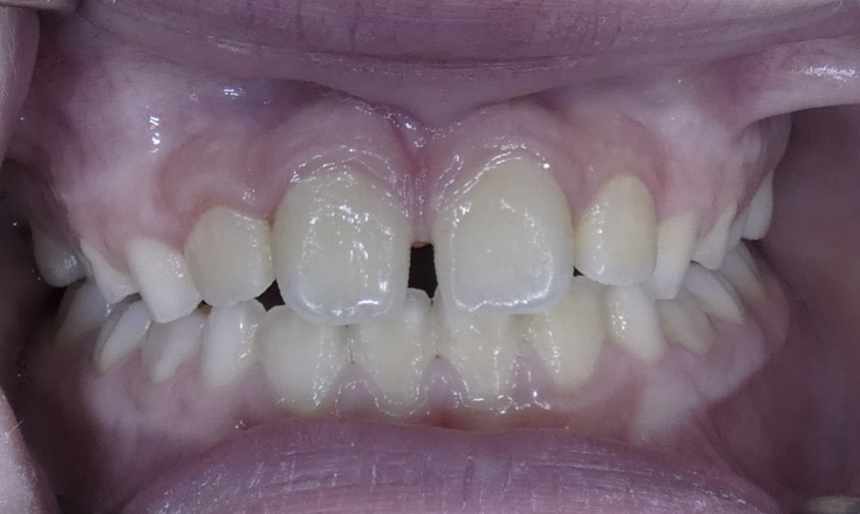

Diastema

Gaps between teeth